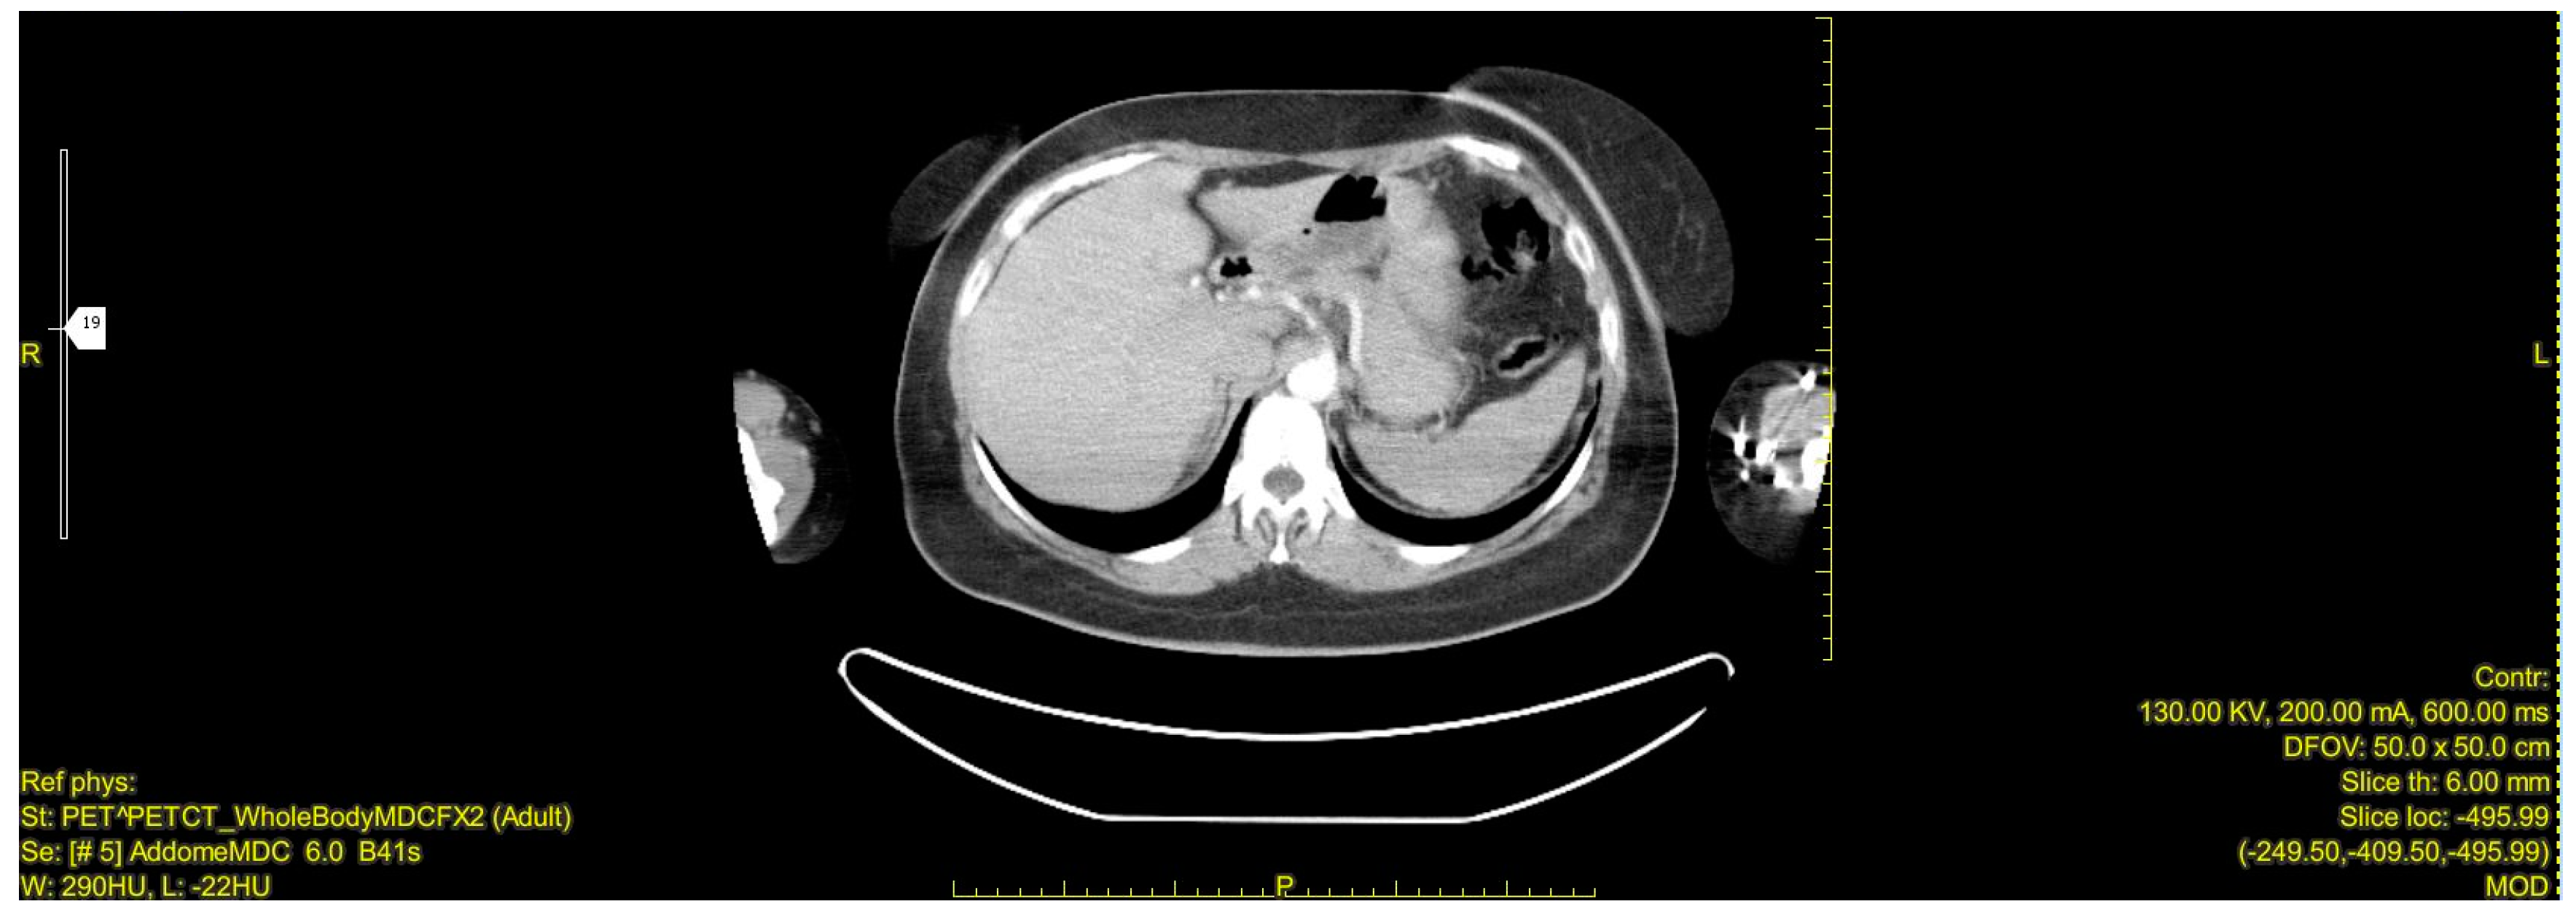

| Our Case Rep | 52 | F | R | 9 × 7 × 6 | None | Laparoscopic Adrenalectomy + Nephrectomy | CT | 12 (alive with liver metastasis) |